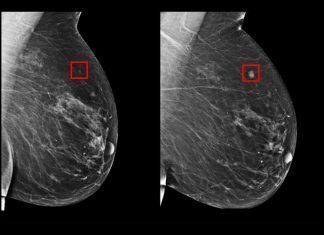

La Inteligencia Artificial que predice si una mujer padecerá cáncer de mama en el...

Buenas nuevas han surgido a través de la tecnología, para la

medicina oncológica. La Inteligencia Artificial, vista como herramienta

potencial para descifrar casos de cáncer, vuelve a demostrar su valía. En este

caso, prediciendo de una manera...